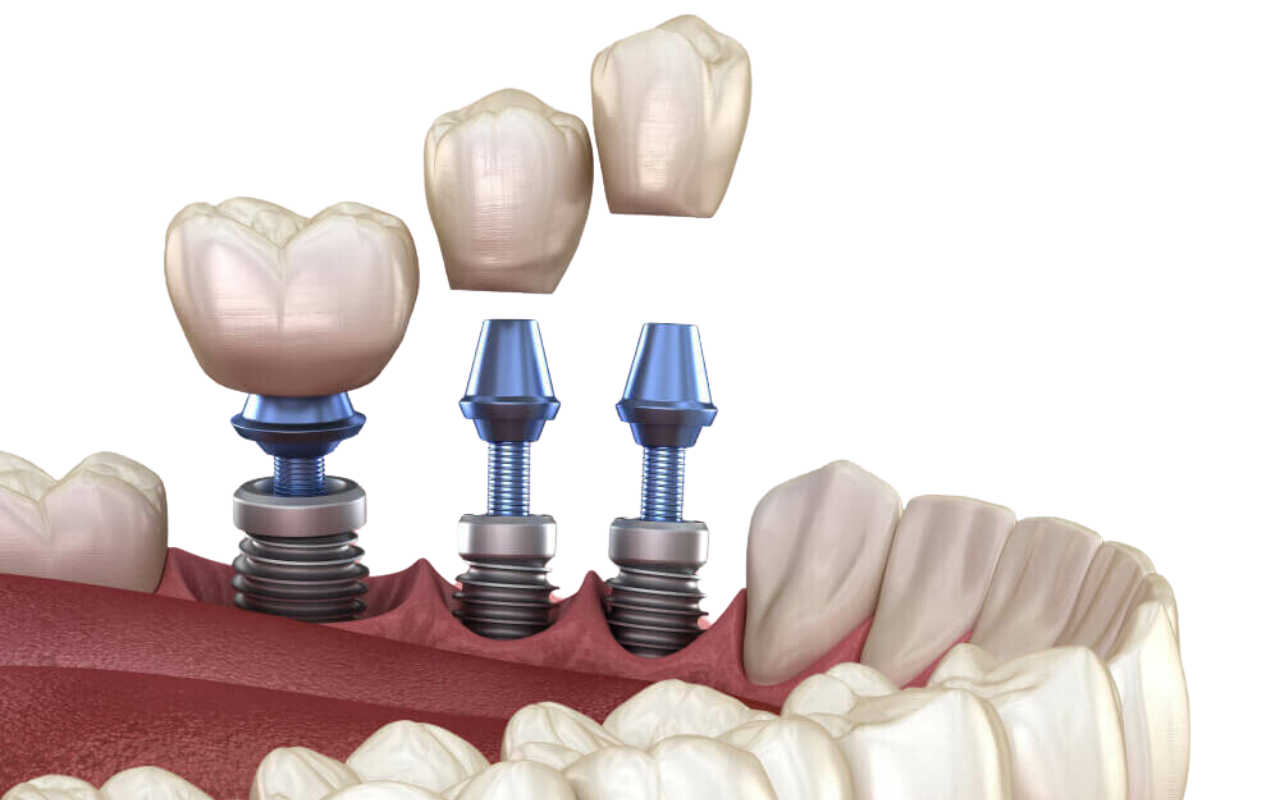

With over a decade of experience in all fields of dentistry, Dr. White has a particular passion for cosmetic procedures, including dental implants, Lumineers, and Invisalign. His extensive experience in private practice and dedication to helping those in need have honed his skills in delivering exceptional dental care. Patients choose Dr. White for his ability to not only alleviate pain quickly but also to dramatically improve their smiles and quality of life through expertly performed dental implants.